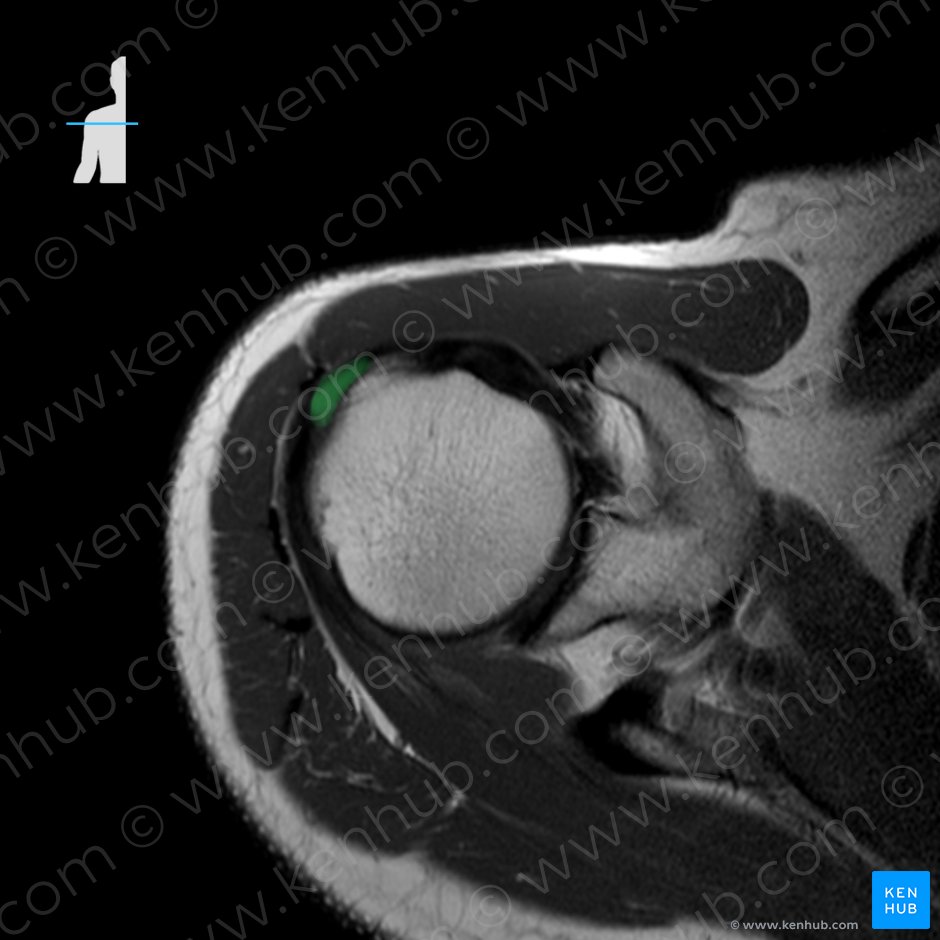

1. 극상근(Supraspinatus, 가시위근)

function : Shoulder joint: abduction of arm,stabilization of the humeral head in the glenoid cavity

견갑하건 바로 아래 위치하는 점액낭의 염증으로 견봉 앞 아래쪽에 위치합니다. 견관절 염증에 의해 이차적으로 발생할 수 있으며, 만성적인 나쁜 자세습관(ex. 운전 자세)에 의해 발생할 수 있습니다. 초음파로 진단하며, targeting 하여 치료할 시 매우 효과적입니다.

** 회전근개 파열

뼈에 붙어 있는 회전근육의 힘줄이 노화 현상같은 퇴행성 변화가 일어나 파열까지 이르게 되는 질환을 회전근개 질환이라 하며 부분파열에서 전층파열로, 소파열에서 대파열로 병이 진행하는 성격을 가지고 있습니다.